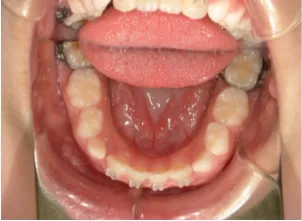

治療中④小2(8y2m)~小3(9y1m):QHとBHで拡大・アーチ形態の修正、ブラケットで前歯の並べ替えまで終了

| 行ったご提案・診断内容 | 成長期に行う治療と咬合治療をご提案 受け口用ファンクショナルアプライアンス(写真②③)からスタートし、小2以降で上下顎の拡大・歯列弓の形態修正・前歯の並べ直し(写真④)を行いその後、モノブロック(筋機能的咬合誘導)装置(写真⑤)へ移行し、受け口の再発予防と永久歯を適切な咬み合わせに誘導し、必要によりマルチブラケット法へ移行する治療方法を提案しました。 成長期治療(成長時期にお口の環境を整える治療) 2年生以降から 咬合治療 |

| 治療期間 | 12か月:受け口用ファンクショナルアプライアンス(写真②③) 12カ月:成長期治療の動的治療期間(写真④) 現在、成長の経過観察と咬合誘導中です(写真⑤~⑨) |